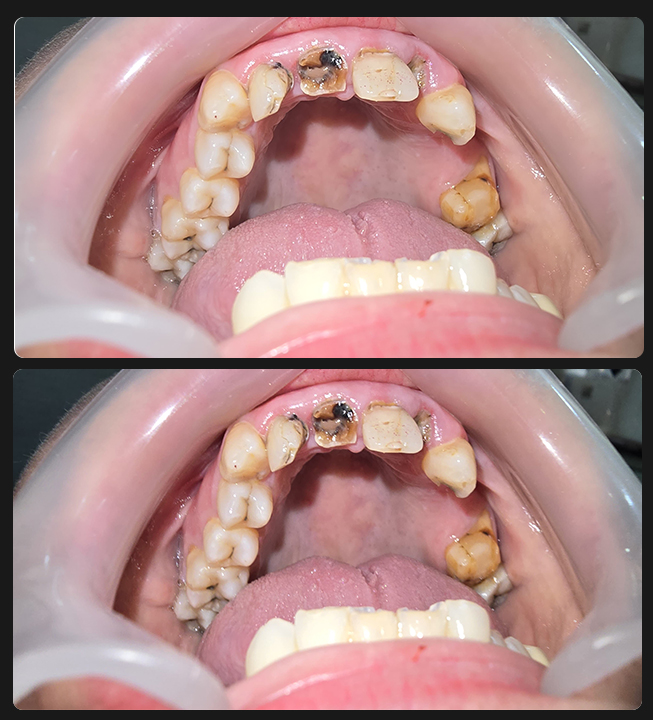

Full Mouth Zirconia (All-Ceramics)

Case 1

Case 2

Case 3

Case 4

Case 5